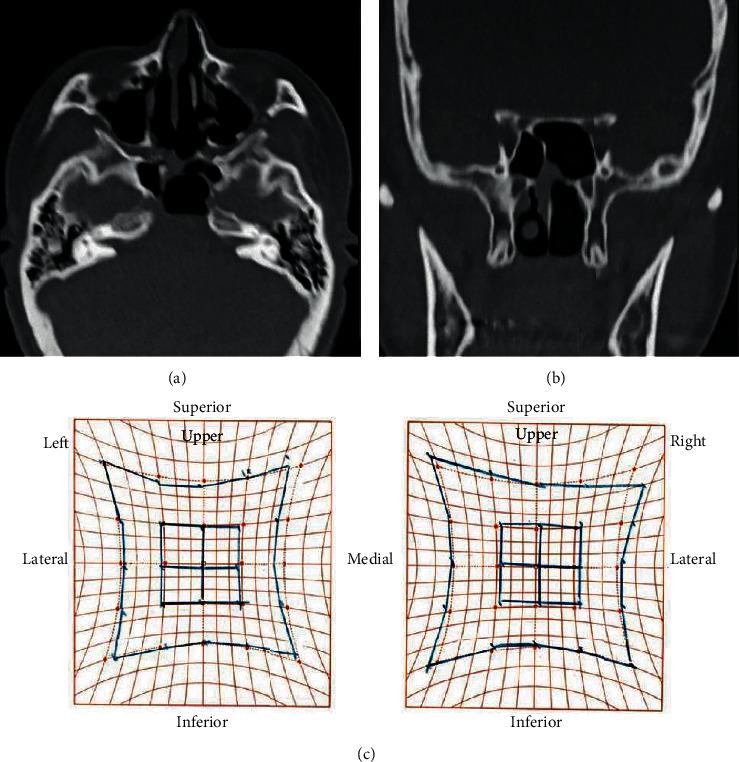

Primary solitary sphenoid sinus mucocele is rare, generally presenting with headaches or eye symptoms at the anatomical site. We report the case of a 39-year-old woman incidentally diagnosed with sphenoid sinus mucocele during a complete medical checkup. Imaging revealed that the cystic wall had developed from the rear sphenoid sinus and had spread expansively to diminish the clivus; however, no symptoms were reported, and the patient was managed with close observation. During the follow-up period, diplopia developed suddenly due to isolated left-sided abducens nerve paralysis. An endoscopic endonasal approach was used to open the frontal cystic wall, and fascia lata and fat were used for cranial base reinforcement to avoid future cerebrospinal fluid leakage, resulting in improvement during the early stages of follow-up. Treatment options for sphenoid sinus mucoceles include close observation or surgery. In our case, we chose surgery because of an acute symptomatic manifestation during observation.

原发性孤立性蝶窦黏液囊肿罕见,通常在解剖部位出现头痛或眼部症状。我们报告了一例39岁女性在全面体检时偶然诊断为蝶窦黏液囊肿的病例。影像学检查显示,囊肿壁由后蝶窦发展而来,并呈膨胀性扩展,致使斜坡骨质吸收;然而,患者并无症状报告,遂对其进行密切观察。在随访期间,患者突然因孤立性左侧展神经麻痹出现复视。采用鼻内镜经鼻入路打开额部囊肿壁,并使用阔筋膜和脂肪进行颅底加固,以避免未来脑脊液漏,在随访早期病情有所改善。蝶窦黏液囊肿的治疗选择包括密切观察或手术。在我们的病例中,由于观察期间出现急性症状表现,我们选择了手术治疗。